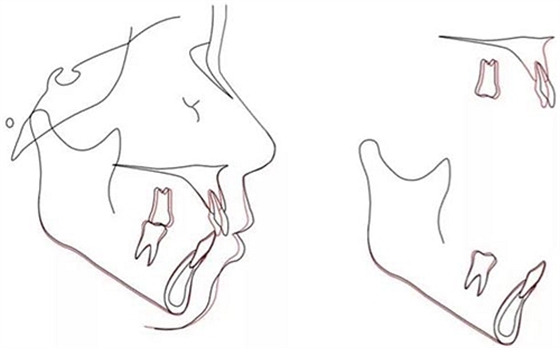

該患者在6顆上前牙區(qū)使用雙J鉤片段弓,水平臂均用0.028-in不銹鋼絲制成,作用力在臂的最末端,力的模擬見圖4。使用該方法能夠模擬正畸時(shí)受到的力。文獻(xiàn)表明,TAD深度8mm為佳,前牙阻抗中心由牙齒移動模式?jīng)Q定水平臂的末端而決定。圖4顯示了6顆前牙在內(nèi)收4mm后牙周膜的應(yīng)力分布。當(dāng)力的延長線通過6顆牙的阻抗中心是,牙齒整體移動且壓低0.5mm,當(dāng)其處于阻抗中心冠方時(shí),前牙舌傾,當(dāng)其處于根方時(shí),根舌向移動。(圖5)

治療后頭側(cè)數(shù)據(jù)提示:無明顯骨性變化(上頜SNA82.1°,下頜SNB74.9°),上頜前牙得到內(nèi)收,略舌傾,頦部前后位置無明顯改變,仍未凸面型(圖8,表)。將治療前后圖像重疊后結(jié)果如(圖8及圖9),24月后隨訪結(jié)果見圖10.